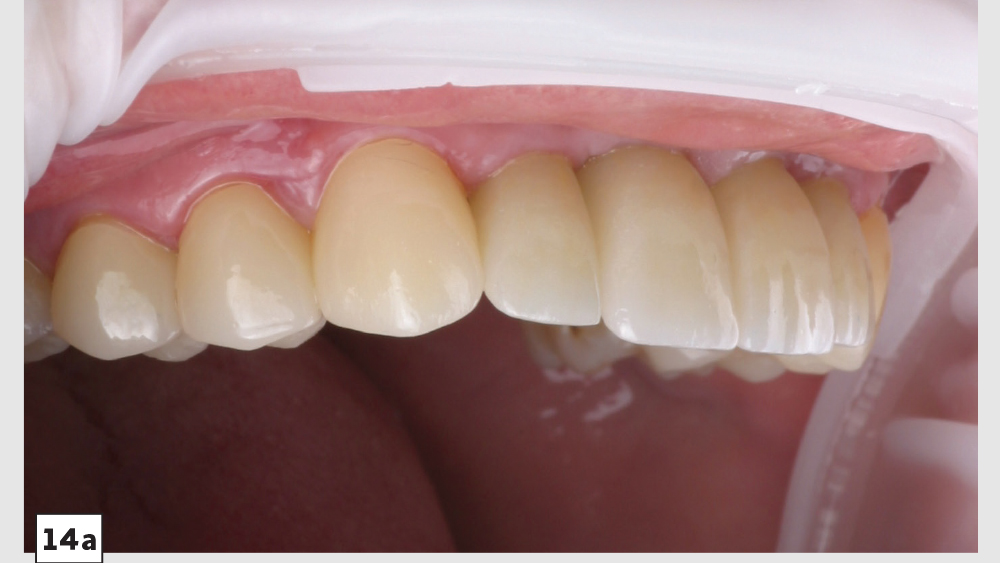

This patient came to me with four missing anterior teeth in positions #7–10. He had been missing these teeth for some time and was wearing a temporary denture to address the cosmetic issue this created. When he came to my practice, he was in a financial position to solve the problem permanently with implant restorations. Based upon the anterior space available and the fact that the patient’s surrounding tissue was in good health, I chose to move forward with Hahn™ Tapered Implants and BruxZir® Esthetic restorations.

There’s nothing more rewarding than when patients return to your office for additional dentistry because they were so thrilled with the results of the previous procedure you performed for them. This particular patient followed through with the additional treatment I had previously recommended.